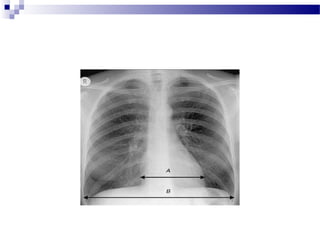

 Marginea superioara a

scizurilor oblice (B) bilateral

 Scizura orizontala dreapta (A)

si marginile inferioare (B) ale

scizurilor oblice bilaterale

 ambii plamani sunt suprapusi,

luati separat, plamanul stang

are o singura fisura oblica

 plamanul drept are ambele

fisuri, oblica si orizontala

 Indicele cardiotoracic trebuie să fie mai mic de 0,5

 ICT= A/B

 Un ICT mai mare de 0,5 (pe un film executat corect) sugerează

cardiomegalie